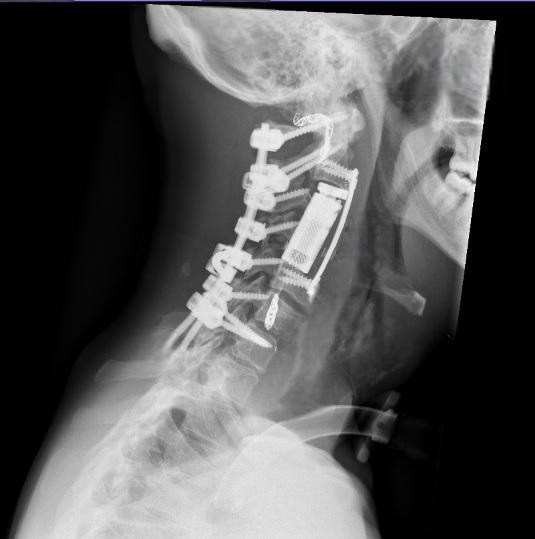

وفي المرحلة الجراحية، تم إجراء تثبيت خلفي للعمود الفقري من الفقرة العنقية الأولى وحتى السابعة، مع تحرير النخاع الشوكي وتأمين استقرار الفقرات. بعد ذلك، أُجري استئصال كامل للورم والفقرات المصابة بطريقة “الاستئصال الكامل في كتلة واحدة” (En Bloc Resection) عبر المدخل الأمامي للعنق، تلاه تعويض الفقرات باستخدام قفص فقري تمددي (Expandable Cortectomy Cage)، مع تثبيت أمامي لضمان الثبات الكامل للعمود الفقري.

وأكد أن هذه العملية تُعد الأولى من نوعها في الأردن والمنطقة، ولا تُجرى إلا في المراكز المتقدمة على مستوى العالم، نظرًا لتشريح الورم المعقد، إذ شملت استئصال أكثر من فقرة عنقية إضافة إلى الشريان الفقري المصاب المجاور للورم.